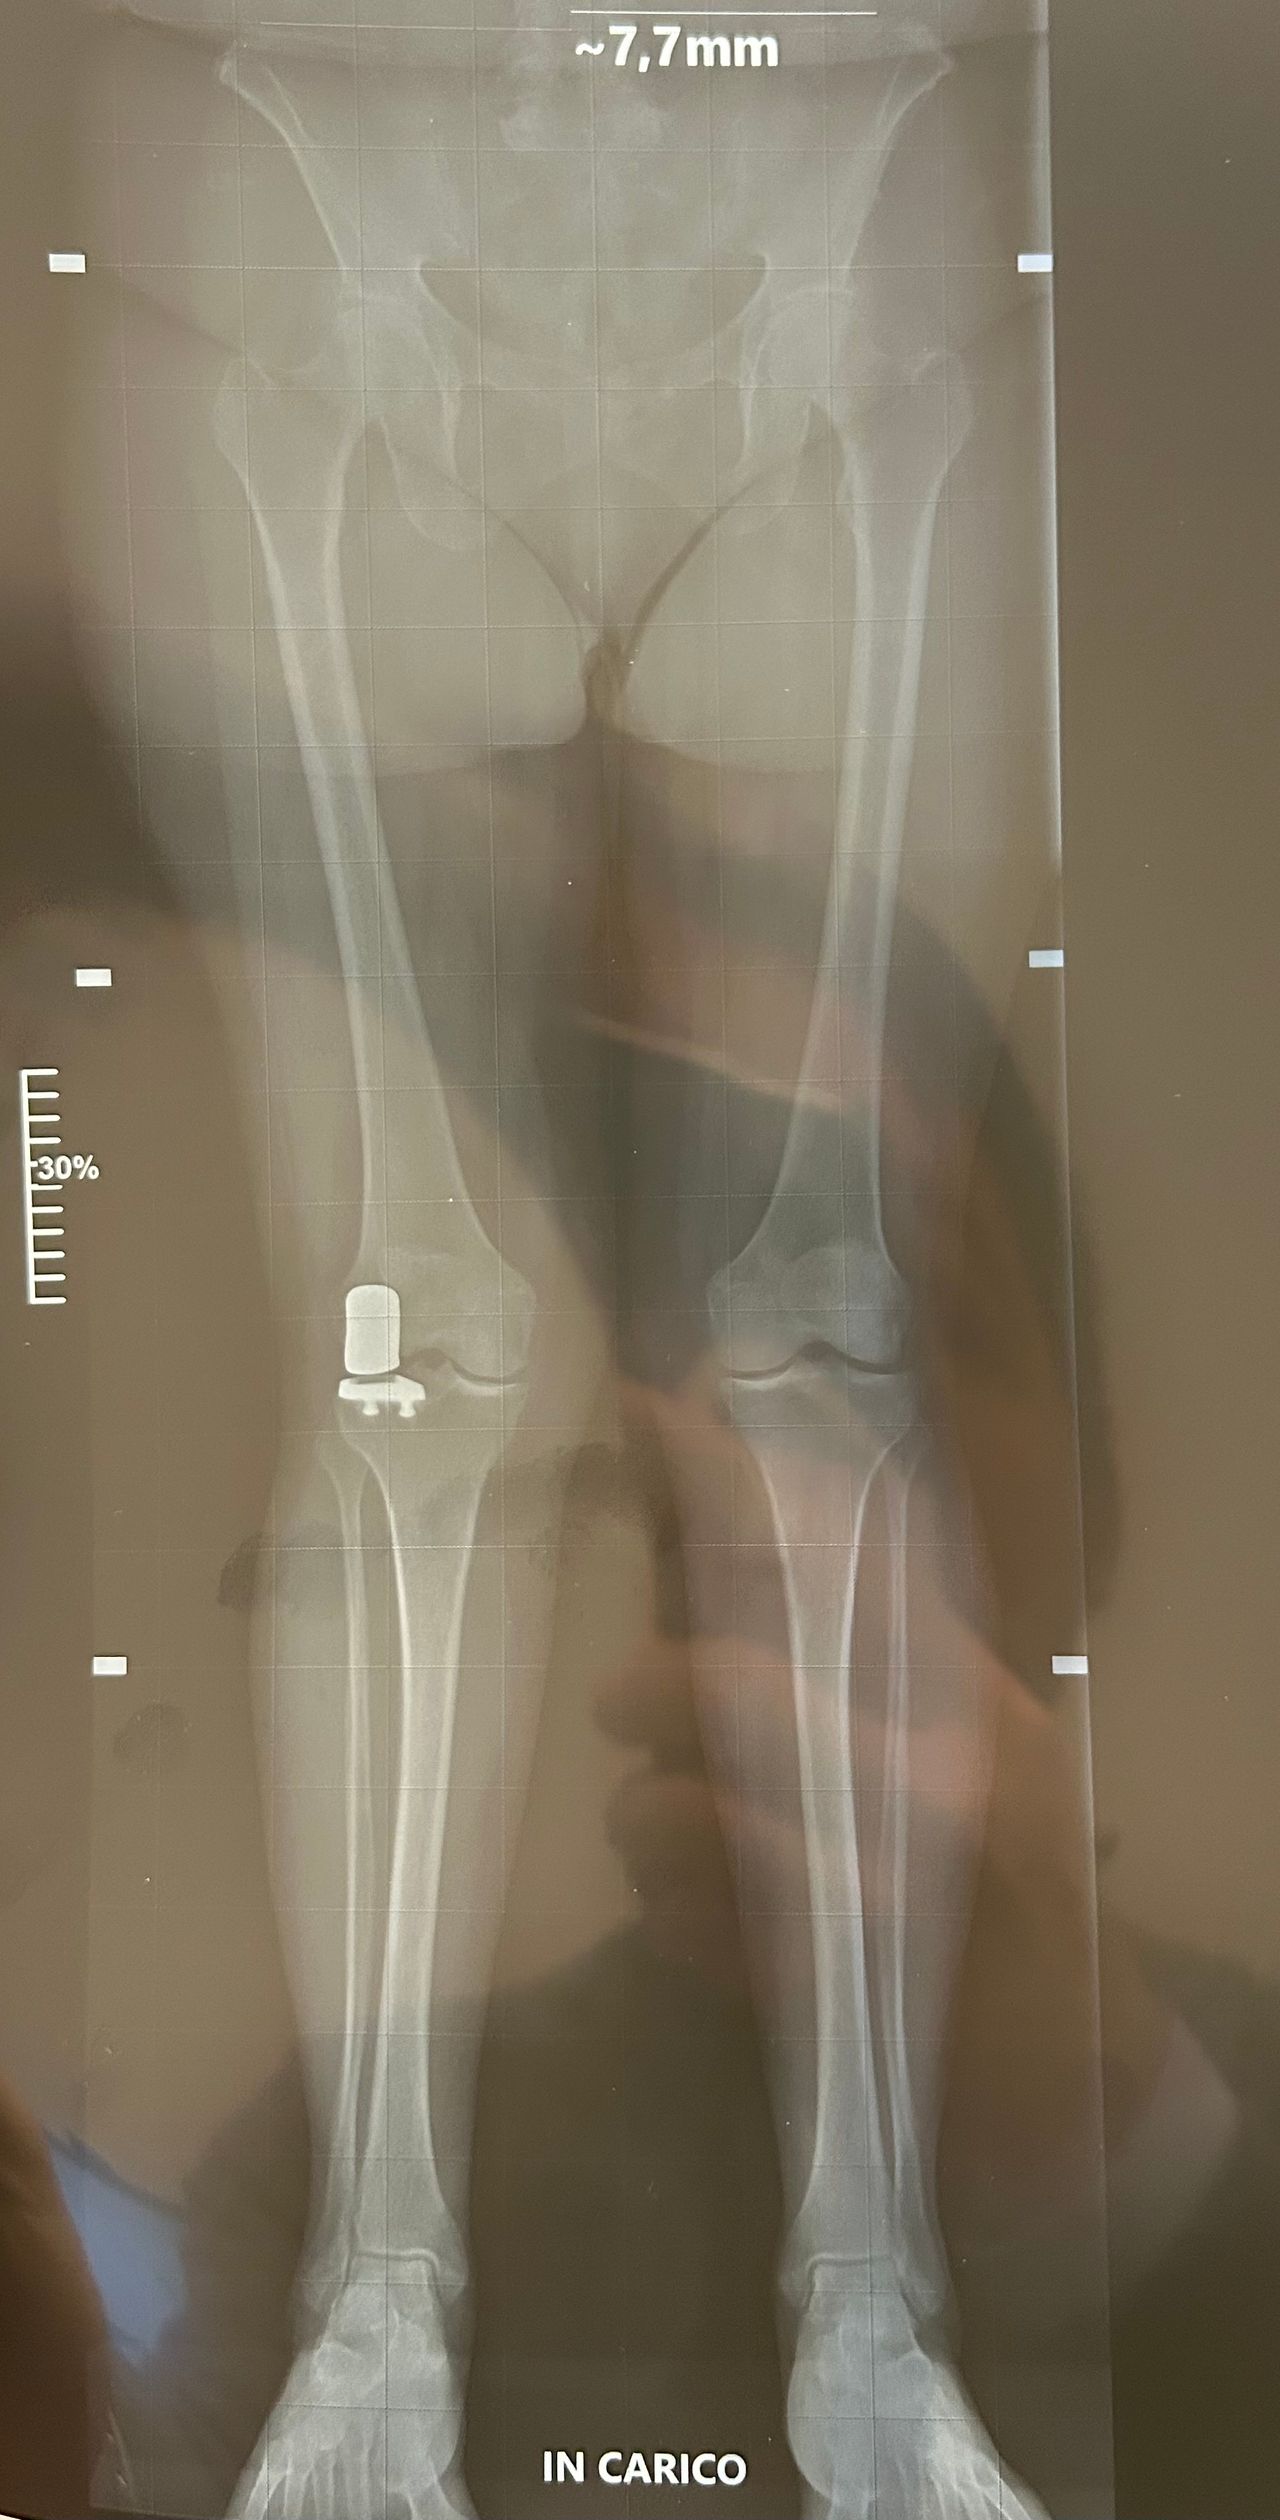

Foto e video

Per una maggiore completezza della visita è utile avere a dispozione almeno una Radiografia standard o Risonanza Magnetica recenti.